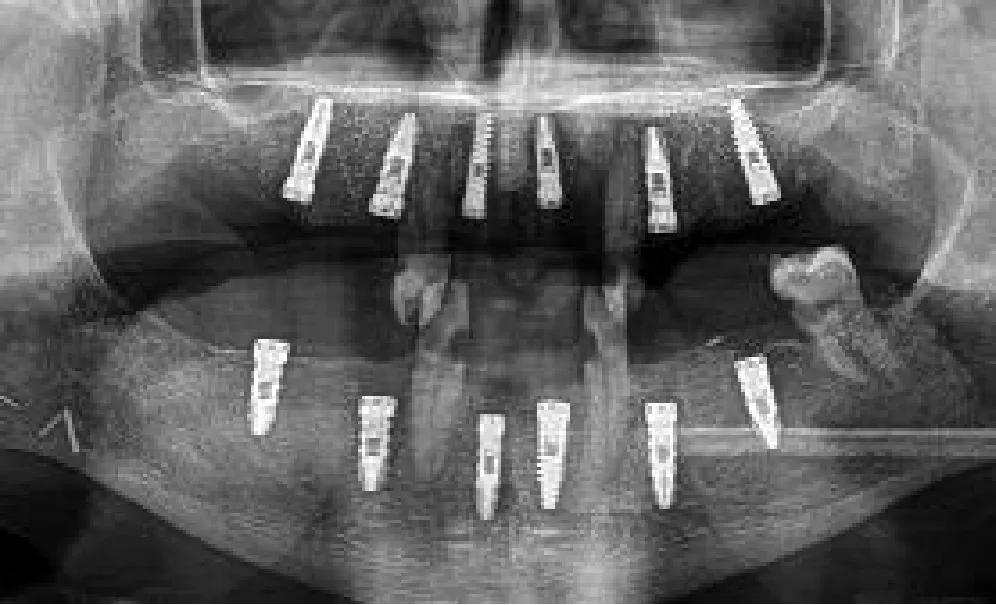

A bimaxillary CBCT scan was acquired for each patient (Figure 1A). Then, impressions of both arches were taken with either silicone or alginate materials, and the plaster was scanned to obtain 3D digital models with a D700 3Shape® scanner. These 3D models were manually aligned with the CBCT scan using anatomical landmarks. Then, VSP was performed on a computer workstation for optimal prosthetically guided dental implant placement using either Nobel Clinician-DTX® studio implant licensed software or Blue Sky Bio® open software (Figure 1B). VSP started with the virtual screw-retained prosthesis design. Once teeth are in the ideal occlusal position, implant locations were defined, focusing on achieving an appropriate angulation and depth while avoiding any interference with osteosynthesis screws. Finally, we ended with a virtual objective of treatment (Figures 1C–F). In all patients we placed Ticare®Osseous (Mozo-Grau, SA, Valladolid, Spain) and Ticare®Osseous Quattro (Mozo-Grau, SA, Valladolid, Spain).

We placed a total of 56 implants, 25 in the upper jaw, and 31 in the lower jaw. 18 implants were inserted into the fibula bone (conventional or double barrel), 6 into the iliac crest, and 32 in the patient remnant bone; 15 implants were placed in irradiated bone (1 fibula and the ALT with vastus lateralis case).

The average crestal point insertion error (Table 2) was 1.96 mm, with values between 0.35 and 4 mm (standard deviation 0.95 mm). The combination of static and dynamic navigation offers the best accuracy with an average error of 1.52 mm. Static alone has a 1.56-mm average error, and only-dynamic procedures raise the error to 2.7 mm.

The endpoint or apical deviation error (Table 3) was 2.66 mm, with a range from 0.62 to 7.5 mm (standard deviation 1.33 mm). Considering different guiding techniques, static shows the best accuracy (1.27 mm), followed by the combination with a 2.94-mm error and dynamic alone (3.94 mm).

The angular deviation (Table 4) average error was 8.98°, ranging from 1.4° to 30° (standard deviation 5.38°). The combination of static and dynamic and the static alone shows a similar accuracy (8.07 and 8.1 degrees, respectively). Only-dynamic navigation has a 10.5° average error.

Table 5 summarizes the results for angular deviation and crestal and apical deviation. Each variable is subdivided into three groups for descriptive data analysis: static-guided surgery or dynamic navigation alone, and the combination of both.

A fixed screw-retained prosthesis has already been placed in five patients as planned, while the last six patients are waiting to complete the osseointegration period. We duplicate the period of osseointegration in irradiated bone.

At the end of the surgical procedure, we were able to display planned implant placement intraoperatively with the AR app on our mobile phone in five patients. The final platform and the insertion point deviation were visually verified in 30 implants. The match between virtual planning and final surgical results was observed and recorded.